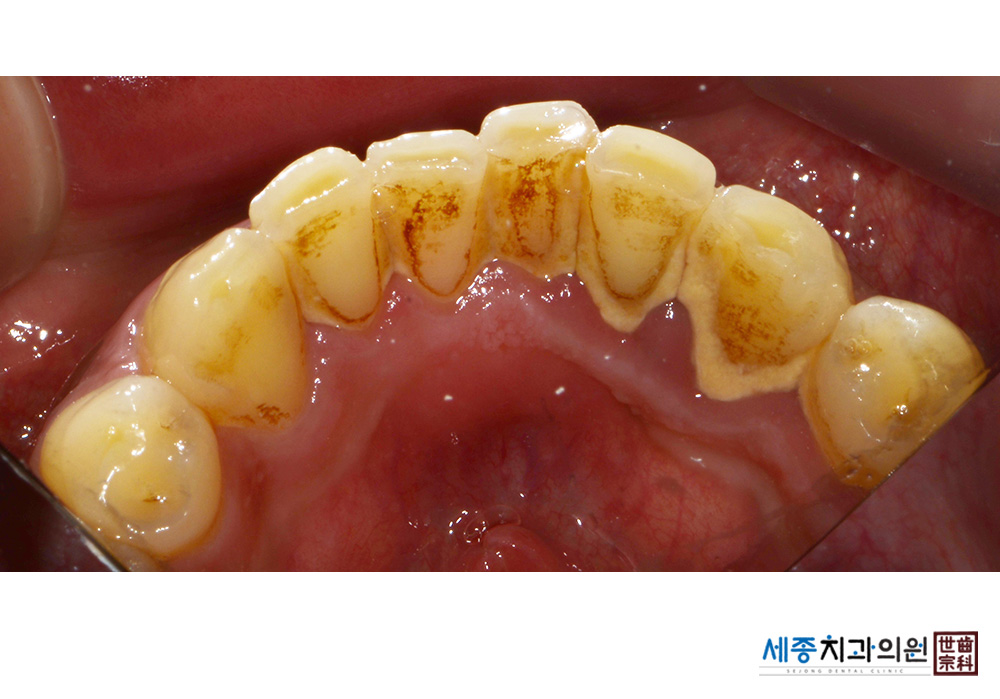

[스케일링] 치주질환 예방 스케일링

치료전 : 2021-01-19

치료후 : 2021-01-19

가글마취&저주파 스켈러를 사용한 스케일링